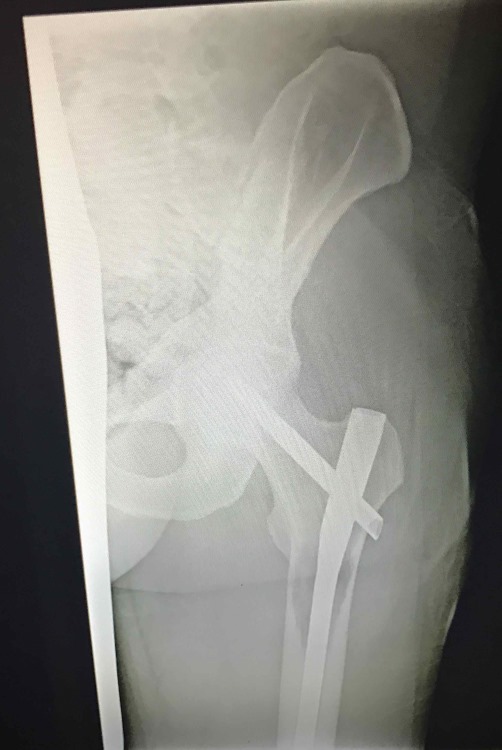

Pic from the femur surgery:

Confirmed via X-ray that my femur isn't losing any more bone. It looks like a tiny bit has grown back, but not much. I'm comfortably walking with the cane now, and driving myself to work. The surgeon says I'm doing really well and expects me to be walking without the cane in 6-10 weeks.